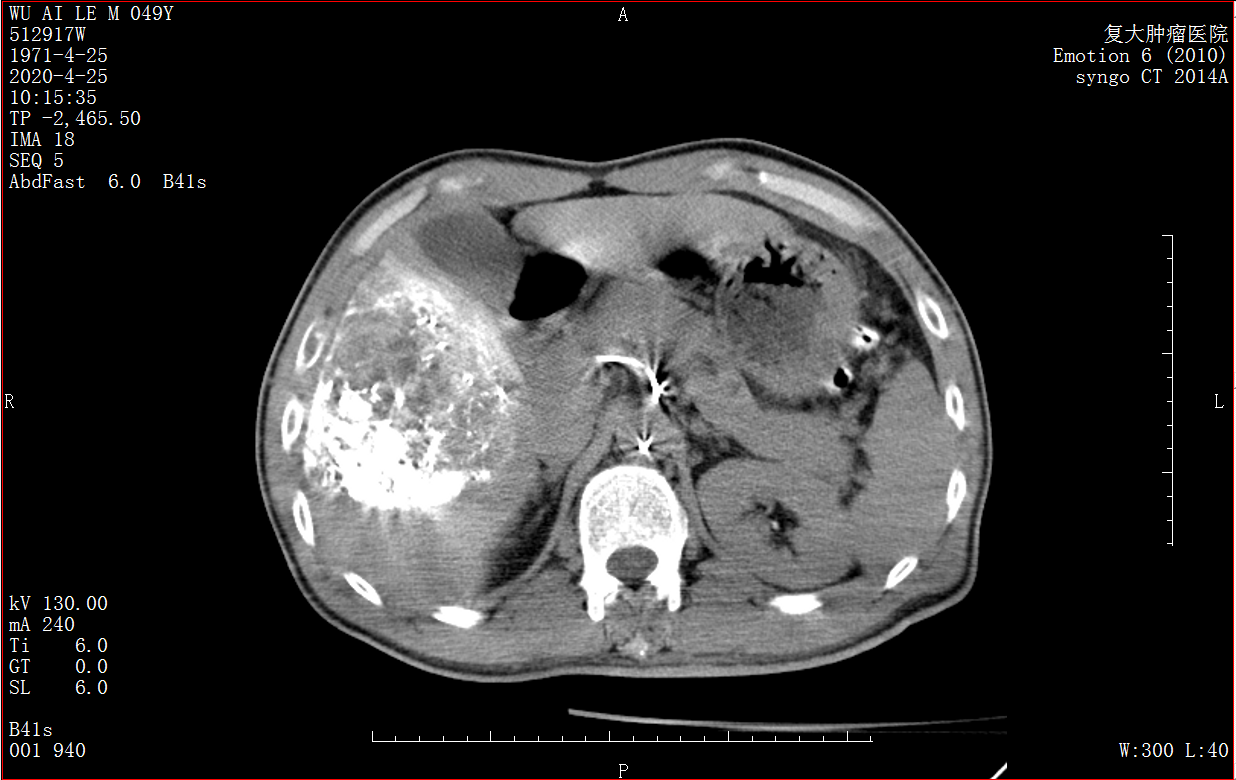

Снимок КТ печени до операции

Снимок MDCT после операции показал, что эмболирующий препарат находится в опухоли печени и все опухоли полностью вылечены, а нормальная ткань печени не эмболизирована, что указывает на отсутствие повреждения нормальной ткани печени.